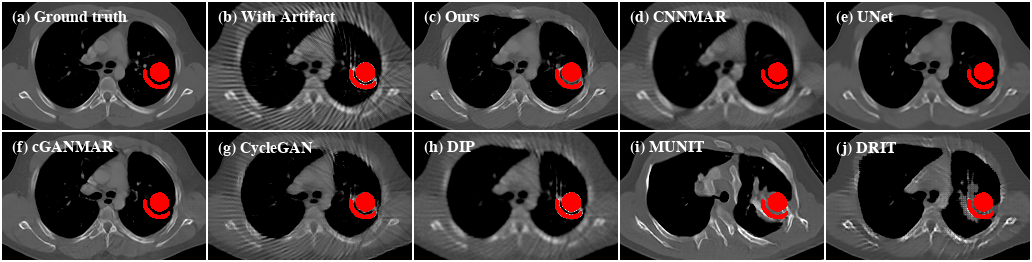

Refer to caption

Figure 9: Qualitative evaluation results of CL1. For better visualization, we obtain the metal regions through thresholding and color them with red.

Performance on clinical data.    Next, we investigate the performance of the proposed method on clinical data. Since there are no ground truths available for the clinical images, only qualitative comparisons are performed. The qualitative evaluation results of CL1 are shown in Figure 9. Here, all the supervised methods are trained with paired images that are synthesized from the artifact-free group of CL1. We can see that UNet and cGANMAR generalize poorly when applied to clinical images (Figure 9(d) and 9(e)). CNNMAR is more robust as it corrects the artifacts in the sinogram domain. However, such a sinogram domain correction also introduces secondary artifacts (Figure 9(c)). For the more challenging cross-modality artifact reduction task with CL2 (Figure 10), all the supervised methods fail. This is not totally unexpected as the supervised methods are trained using only CT images because of the lack of artifact-free CBCT images. Similar to the cases with SYN, the other unsupervised methods also show inferior performances when evaluated on both the CL1 and CL2 datasets. By contrast, our method consistently delivers high-quality artifact reduced results on clinical images.